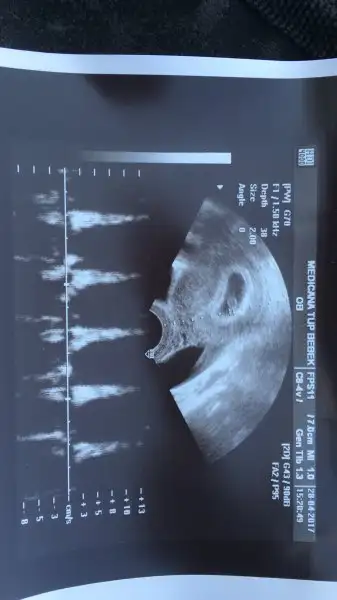

Gözün aydın CNm ben de seni merak ettmiştim:)Selam kızlar Dra gittim bu gün çok şükür kalp atışını çok iyi duyduk bebek 7+2 olması gerek sata göre şu an 6+2 ama kalp atışı da kesede olması gerektiği gibi dedi şükür. Haftaya cuma tekrar bakacak içim rahatladı çok şükür